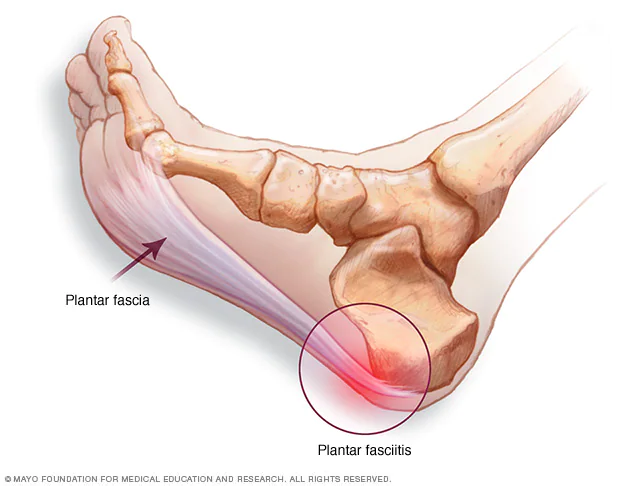

Лечение пяточных остеофитов

Лечение пяточных остеофитов 118 фото